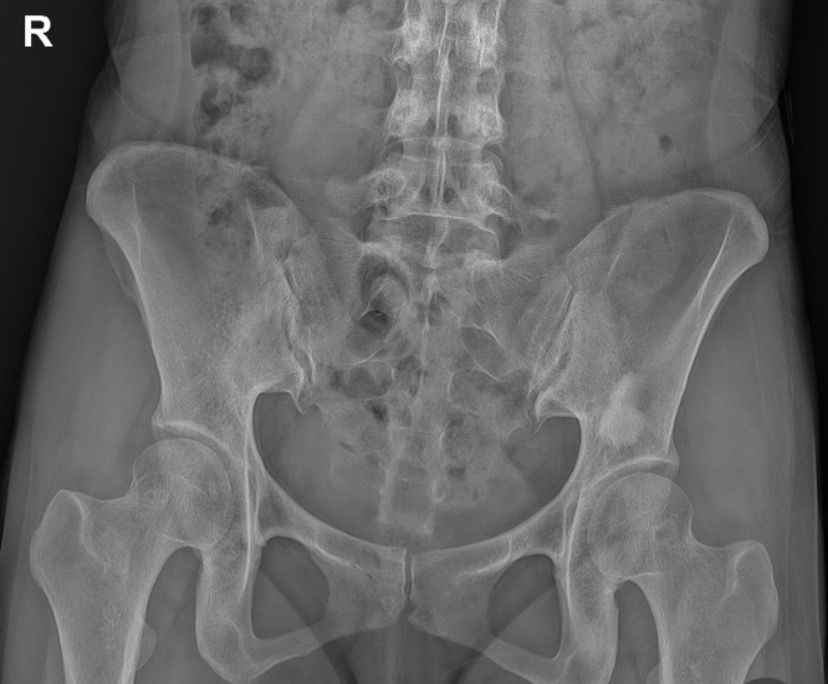

골반 x-Ray 사진 판독 좀 부탁드려요ㅜㅜ

엑스레이 찍자고 하셔서 찍었는데 왼쪽 골반뼈에 뭐가 보인다고 하시더라구요 혹인가… 하시면서 크게 신경 안쓰시는거처럼 말씀하셔서 그런가보다 하고 일단 물리치료 받고 오긴 했는데 시간이 갈수록 조금 걱정이 돼서요…

• 3번 째 사진

혹으로 의심되는 골반뼈 이상이 있다면 정확한 성격 파악을 위해 CT, MRI 검사가 권장될 수 있습니다. 엑스레이는 뼈의 구조만 제한적으로 보여주기 때문에 혹이 양성인지, 염증성인지, 다른 문제인지 구별이 어렵습니다. 통증이 계속되거나 불편감이 심해진다면 정밀검사를 받아보는 것이 안전합니다.